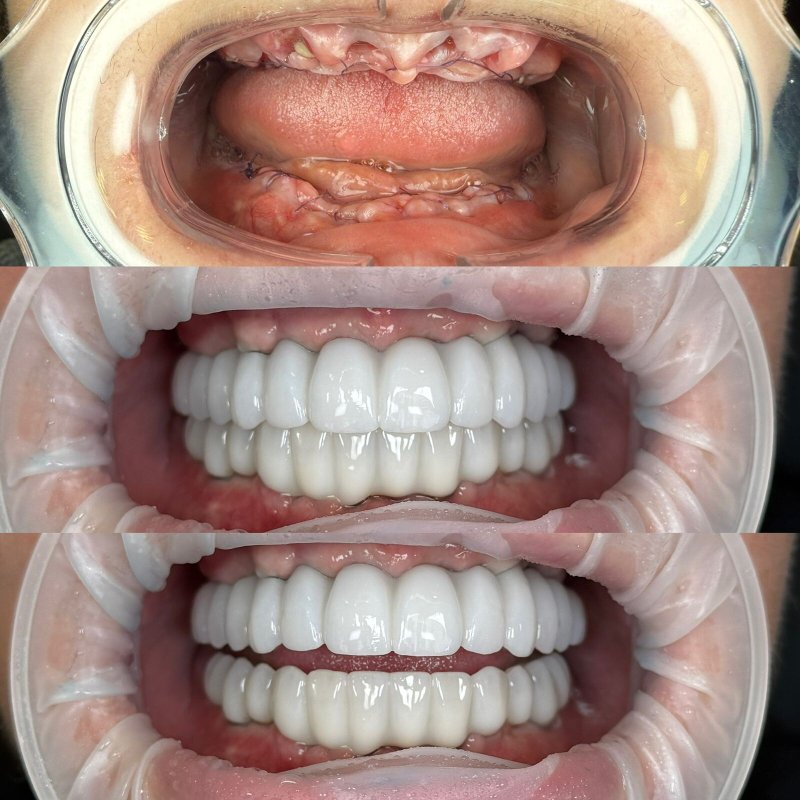

Фотогалерея